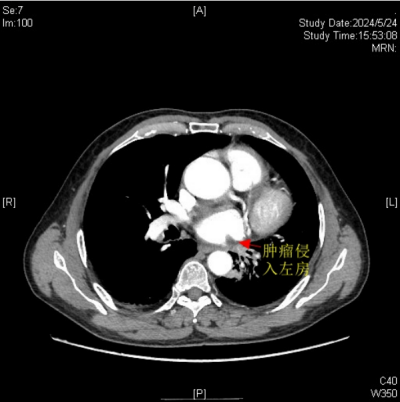

肿瘤侵入左心房

据悉,今年67岁的楚天海(化名)有长达40余年的吸烟史。因反复咳嗽、咯血等症状持续3个月之久,来到香港马会app (南华大学附属香港马会app )胸心外科门诊就诊。经全面检查与评估,诊断他患有左肺中央型鳞癌,且肿瘤有部分侵入左心房,情况凶险。

医院胸心外科主任、主任医师袁跃西表示,由于肿瘤侵入左心房,传统手术方式会因为手术视野受限、可能出现难以控制的大出血风险、肿瘤切除可能不彻底及术后恢复难度大等问题,如何确保患者安全并彻底切除肿瘤,成为了摆在医疗团队面前的难题。